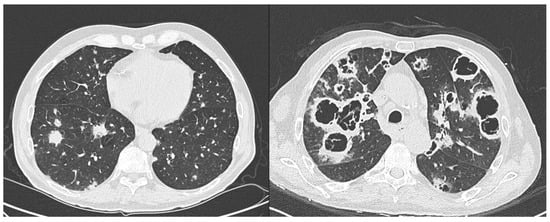

2. Case Presentation